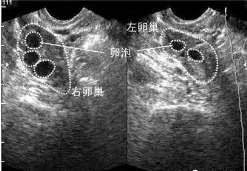

更多相关内容多囊卵巢,幼稚子宫_幼稚子宫能治愈吗生殖中心双子宫先天性发育异常,幼稚子宫_双子宫并发幼稚子宫的可能好大夫在线图文义诊线上诊疗科幼稚子宫_渴望能得到帮助好大夫在线好大夫在线图文问诊生殖中心卵巢发育不全,幼稚子宫_幼稚子宫不来月经好大夫在